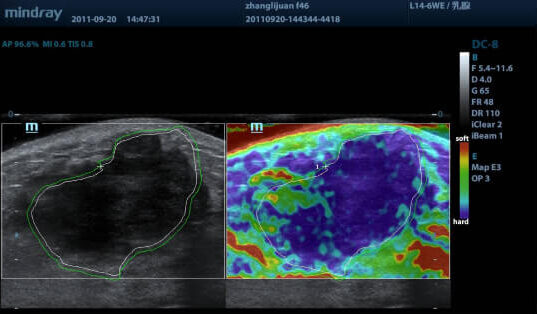

Эластография — технология УЗИ, которая позволяет проанализировать эластичность и плотность тканей. Здоровые ткани обычно упругие и мягкие, а патологические — жесткие.

Компрессионная эластография (NTE) позволяет оценить эластичность поверхностно расположенных тканей (например, молочных и щитовидной желез) за счет дополнительного давления датчиком.

- наличие наглядной цветной карты плотностей тканей;